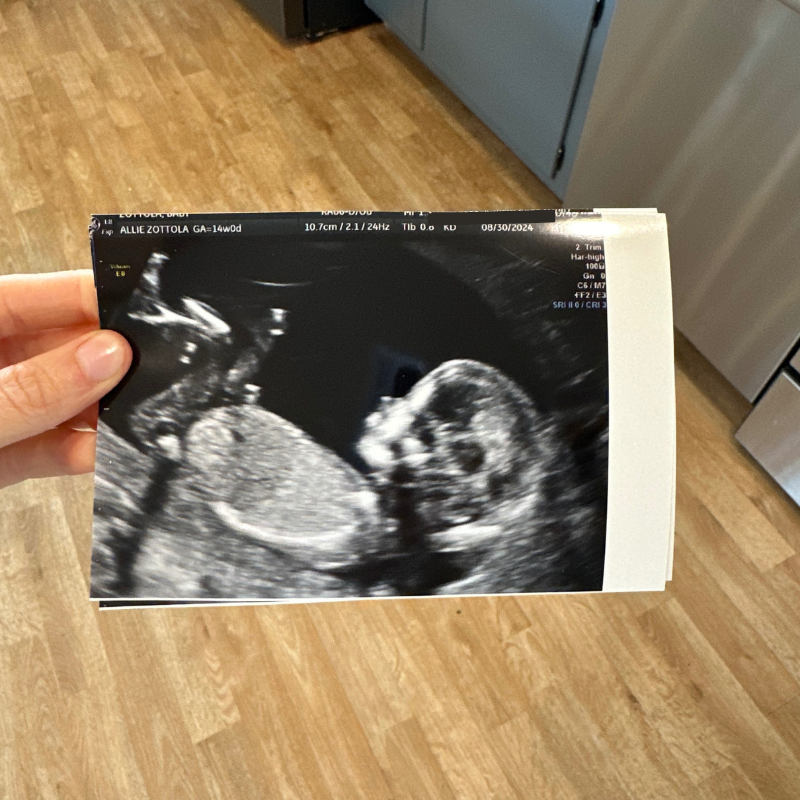

We made it to 14 weeks this week! I think that starts the second trimester?! Baby is now the size of an orange. Sadie loves hearing what the baby’s size is each week. I had an ultrasound done and my mom and Sadie came along and it was so sweet!

Sadie absolutely adored seeing her sister! Baby girl was moving and kicking and even did a headstand?! The ultrasound tech was like “That is one active baby… when you start feeling kicks you are in for it!” haha. Sadie was very similar in utero and I loved it.